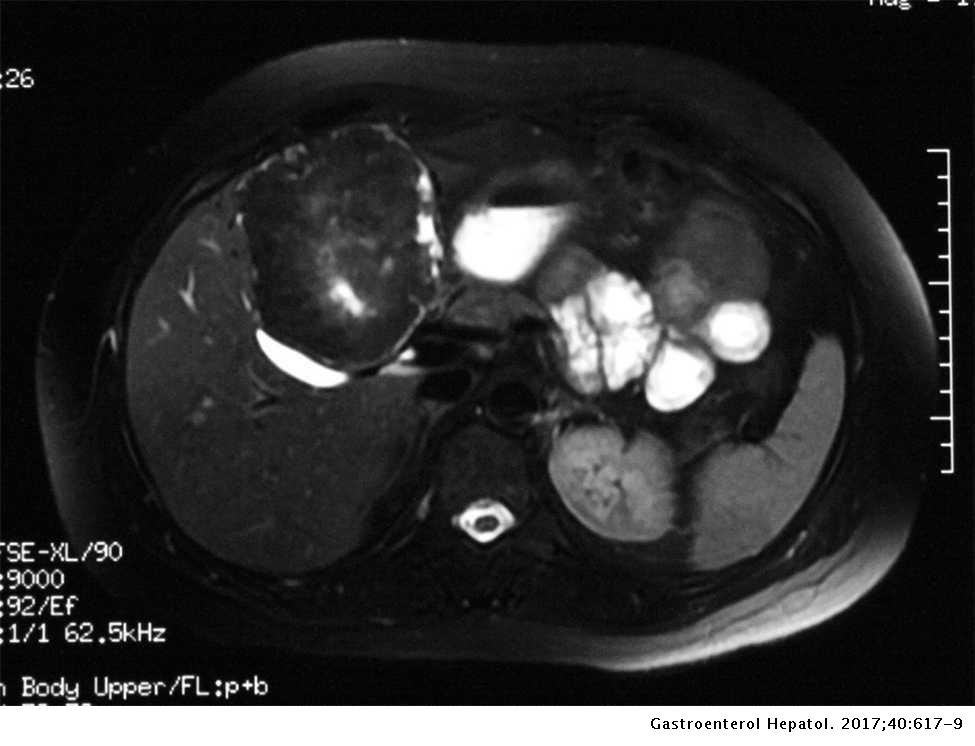

Primary Hepatic Leiomyoma A Rare Liver Mass Gastroenterologia Y Hepatologia English Edition